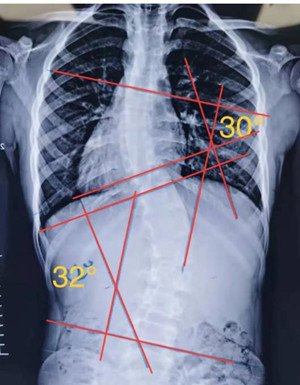

S型侧弯,无论向哪个方向侧躺,对其中一边的弯度都是不利的,这种情况尽量以平躺为主。